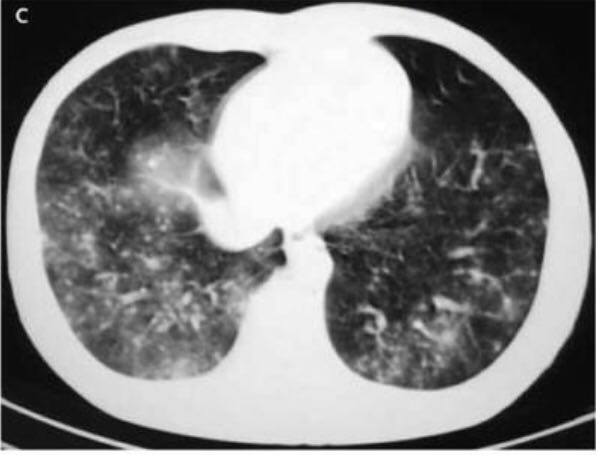

高分辨 CT 显示多个边界不清的结节,直径为 1~5 mm。某些结节聚集融合,周围有磨玻璃样晕征(图C)。